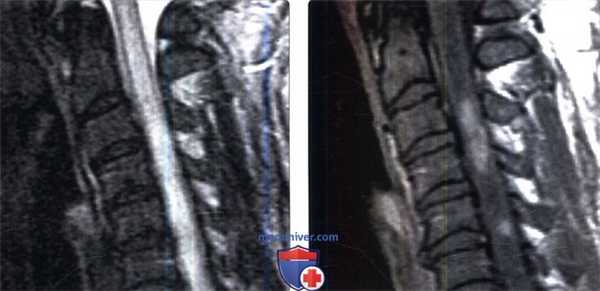

(Слева) Сагиттальный срез, STIR МР-И: патологическое увеличение объема и отек среднешейного отдела спинного мозга на протяжении трех позвоночных сегментов. Участок низкой интенсивности сигнала СМЖ вдоль вентральной поверхности спинного мозга представляет собой артефакт пульсации СМЖ.

(Справа) Аксиальный срез Т1-ВИ с КУ (этот же пациент) отмечается патологическое двустороннее контрастное усиление сигнала центральных отделов паренхимы на фоне патологического увеличения объема шейного отдела спинного мозга.